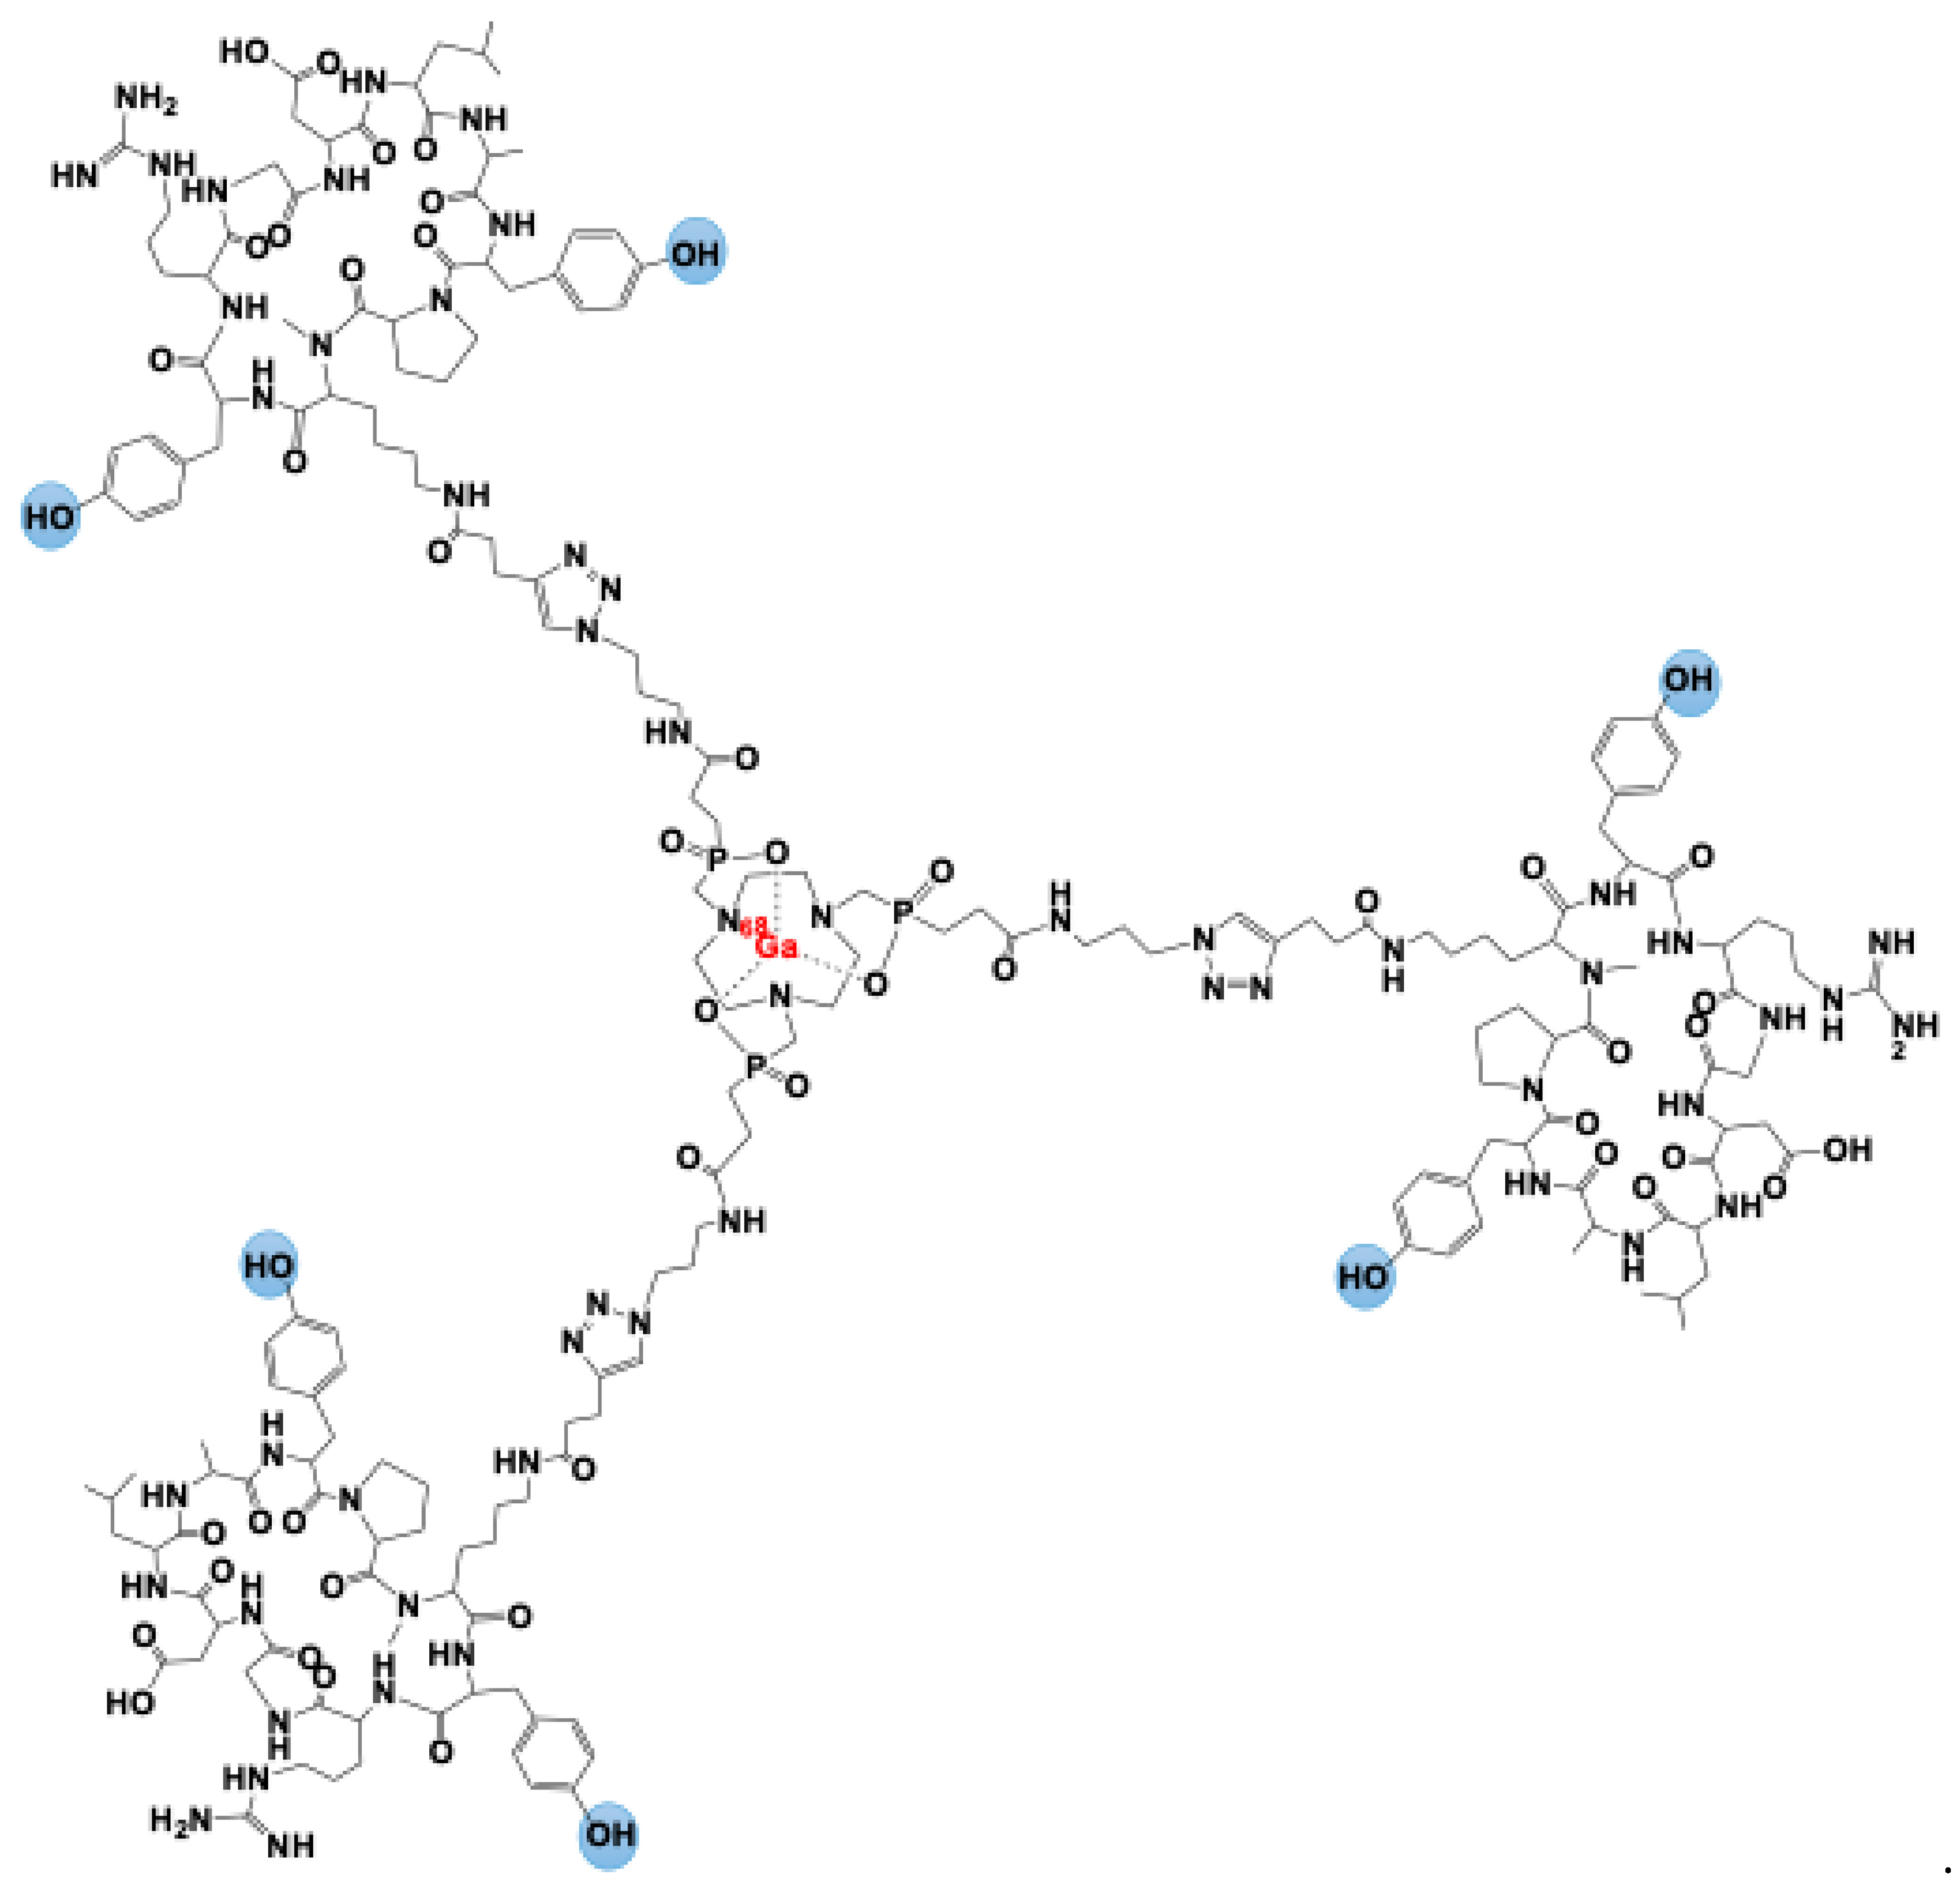

2. [68Ga]Ga-Trivehexin: A Radiochemical Insight